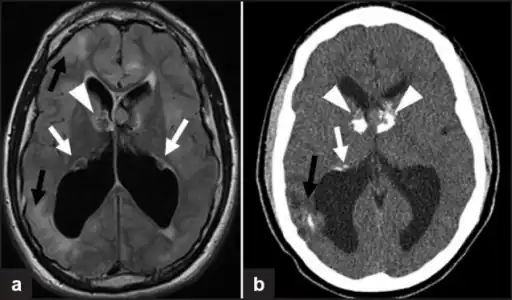

a,b)Images of subependymal giant cell astrocytomas arrowheads -

MRI of brain with sub-ependymal giant cell astrocytoma

Diagnosis is made by imaging with a contrast-enhanced MRI or CT scan of the brain.[3]